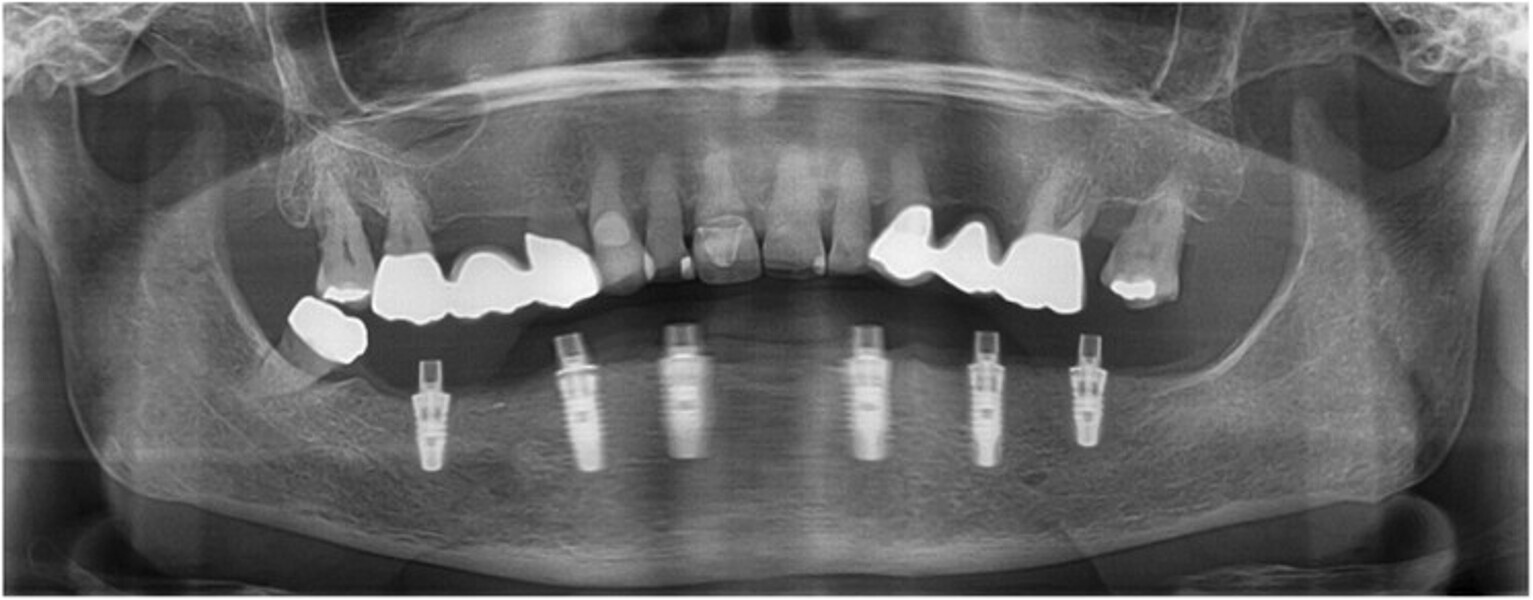

Fig. 1: Panoramic radiograph of the initial dental status.